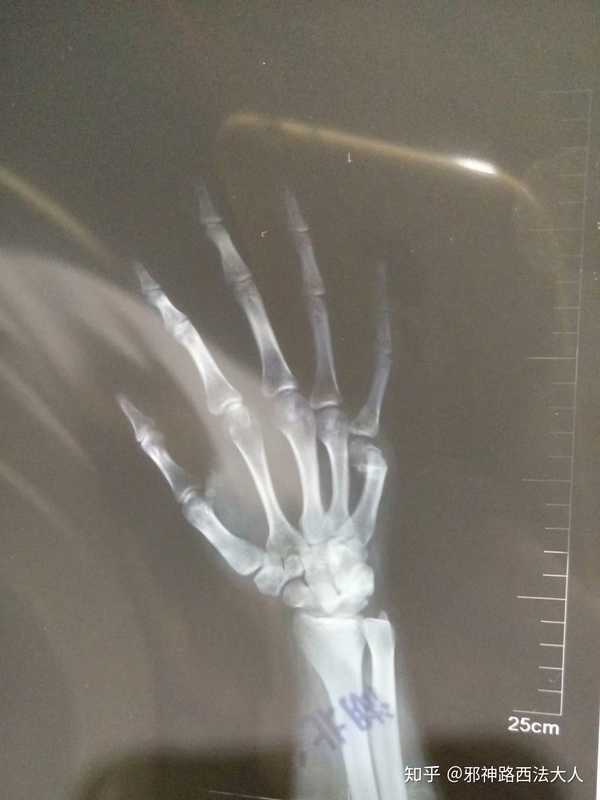

16年8月做的右手第五掌骨闭合复位手术. 附一张当时的x光片.

正常右手x光片

右手x光片